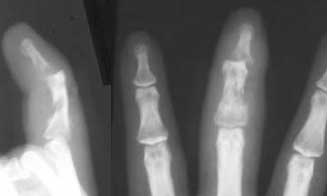

Presenting this case for opinion on management. 34 year old cottage industrialist not able to attend to work following a human bite on his left middle finger one month ago. Patient has received treatment elsewhere where incision, drainage of pus and debridement of sloughed tendons were done along with antibiotics based on culture and sensitivity. At present wounds on the dorsal and volar aspect of middle segment with absent tendons, exposed bones and unstable DIP joint. Infection still present. Stiffness PIP joint present. Clinical picture and xrays attached.

You could consider removing just distal to PIP joint where FDS attaches. Looks like that you have enough soft tissue coverage and that bone is not involved. It should be good cosmetically and not have the functional problem of objects falling out of his palm.